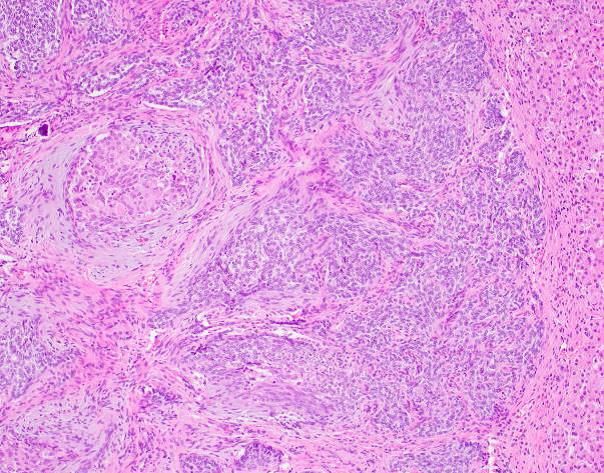

Inflammatory rhabdomyoblastic tumor, initially thought to be a smooth muscle neoplasm in part because myogenin expression is limited - PAX7 is typically diffuse #BSTPath

4

64

162